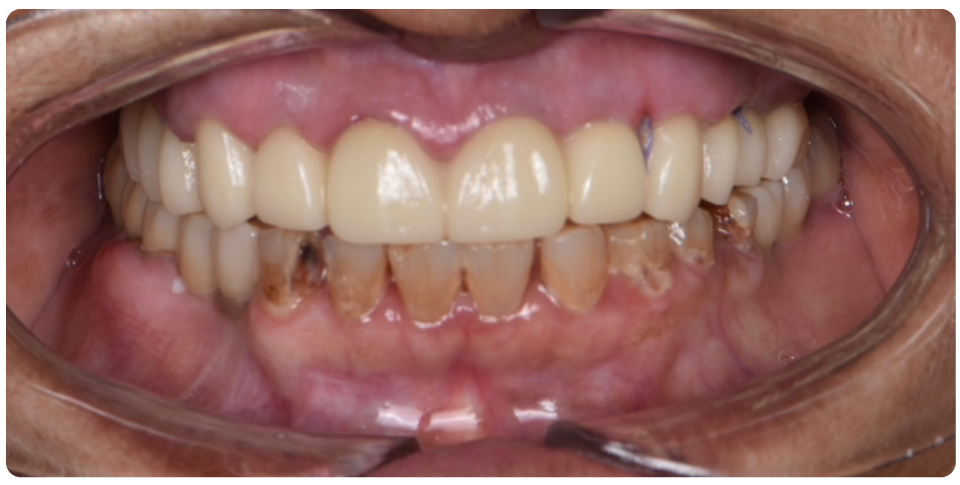

Implant Supported Bridge

An implant-supported bridge is an excellent solution for replacing multiple missing teeth without relying on natural teeth for support.

Instead of traditional bridges that require grinding down adjacent teeth, this option uses dental implants as a strong and permanent foundation.

Benefits of Implant-Supported Bridges:

- Stronger & More Stable – Provides better support and durability than traditional bridges.

- Preserves Jawbone Health – Prevents bone loss by stimulating the jawbone.

- No Damage to Natural Teeth – Adjacent teeth remain intact, unlike traditional bridges.

- Enhanced Function & Aesthetics – Restores chewing ability and a natural-looking smile.

Ideal for multiple missing teeth, implant-supported bridges offer a long-lasting and comfortable solution for restoring your smile.